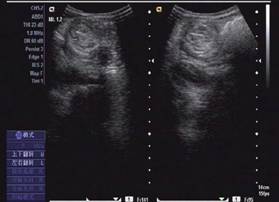

圖示:該患兒當時聲像圖表現(xiàn)

超聲圖像表現(xiàn)

1、腸套疊部位顯示邊界清楚的包塊。其橫斷面呈大環(huán)套小環(huán)的特征性表現(xiàn),即“同心圓征”或“靶環(huán)征”。外圓呈均勻的低回聲環(huán)帶,系鞘部腸壁回聲,低回聲帶系水腫增厚的反折壁及其與鞘部之間的少量腸內(nèi)液體形成。在大的外圓內(nèi),又有一個小低回聲環(huán)帶,形成內(nèi)圓。內(nèi)、外圓間為高回聲環(huán),中心部為高回聲團,其邊緣欠光整。套疊部的縱斷面呈“套筒征”或“假腎征”。有時可能顯示套疊的頂部和頸部,頂部呈指頭狀盲端?!凹倌I征”通常是在套疊時間較長,腸壁發(fā)生嚴重水腫時出現(xiàn),或是成人患者存在腸管腫瘤或息肉時出現(xiàn)。